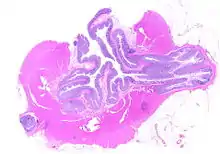

Diverticulosis is the condition of having multiple pouches (diverticula) in the colon that are not inflamed. These are outpockets of the colonic mucosa and submucosa through weaknesses of muscle layers in the colon wall.[1] Diverticula do not cause symptoms in most people.[2] Diverticular disease occurs when diverticula become clinically inflamed, a condition known as diverticulitis.[3]

Pathophysiology

The precise mechanisms by which diverticula are formed are unknown.[1] Multiple theories have been proposed including genetic susceptibility, diet, intestinal motility, changes in the microbiome, and inflammation. One leading theory suggests that diverticula form in weakened areas of the colon wall that are subjected to increased pressure.[1] The strength of the colon wall is known to decrease with age.[1] Previous theories proposed that impacted fecal matter and certain foods would get stuck in diverticula (thereby causing trauma), which caused poor blood flow, death of the affected intestinal wall cells, and intestinal perforation.[1] Newer theories have called this paradigm into question.[1]